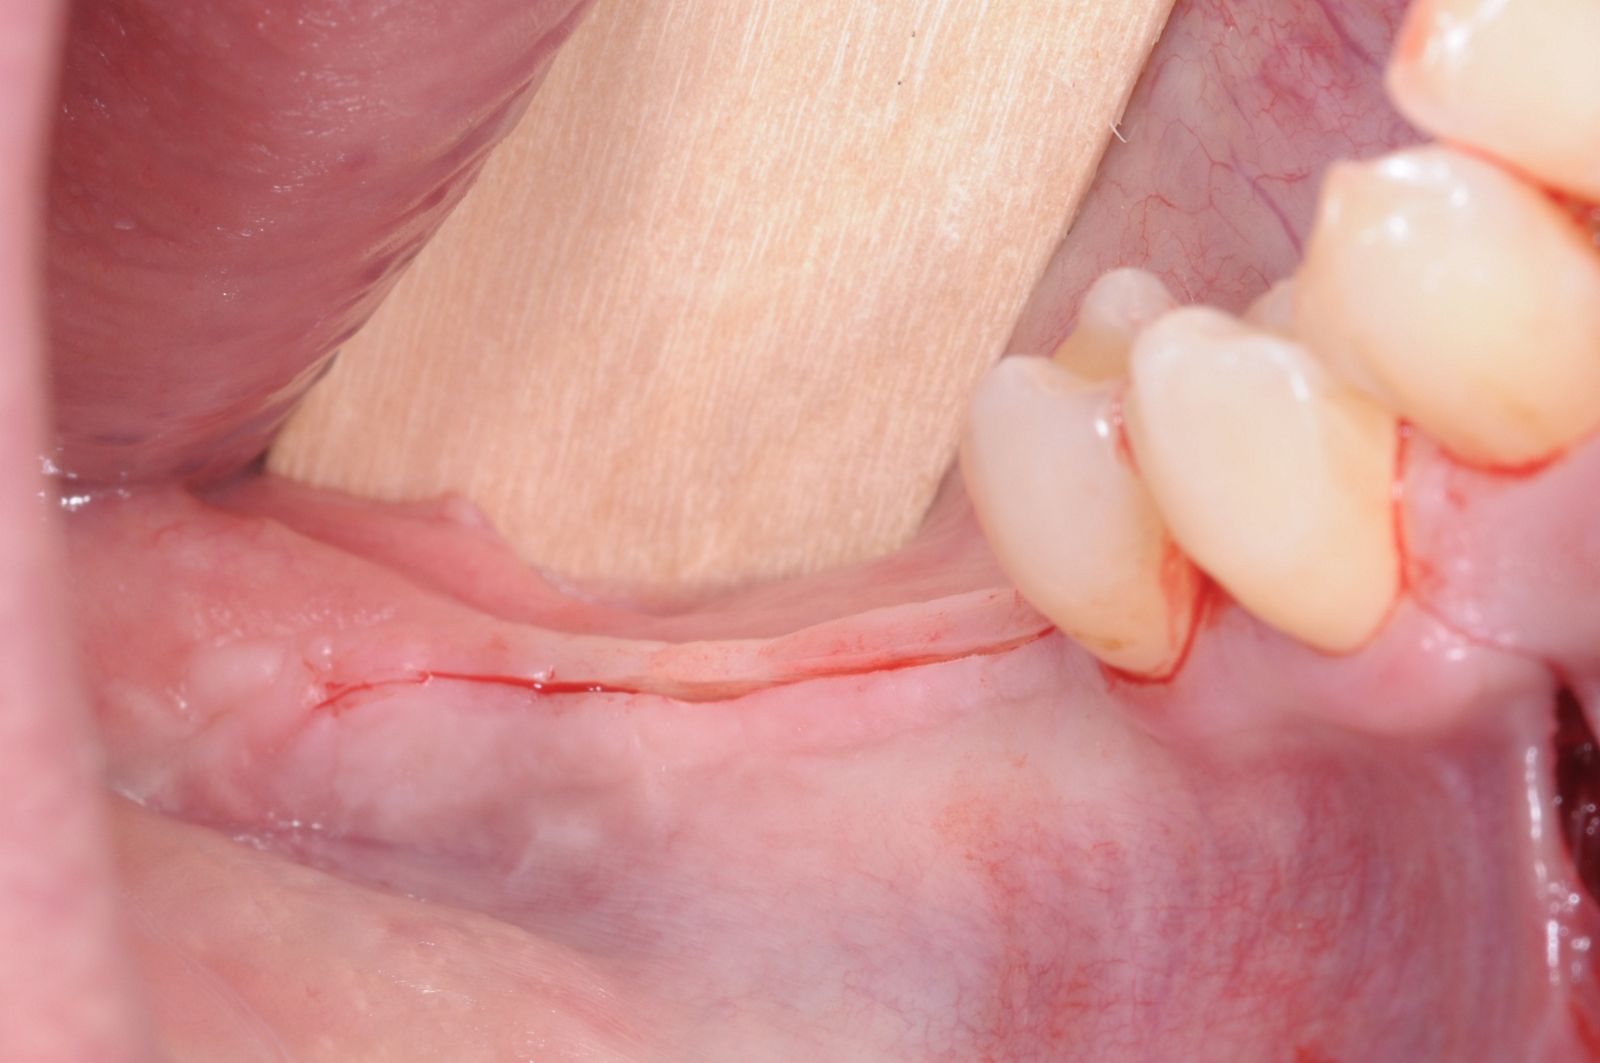

04/28 - Full-thickness flap preparation via crestal incisionThree-dimensional augmentation with maxgraft® cortico - Dr. R. Würdinger